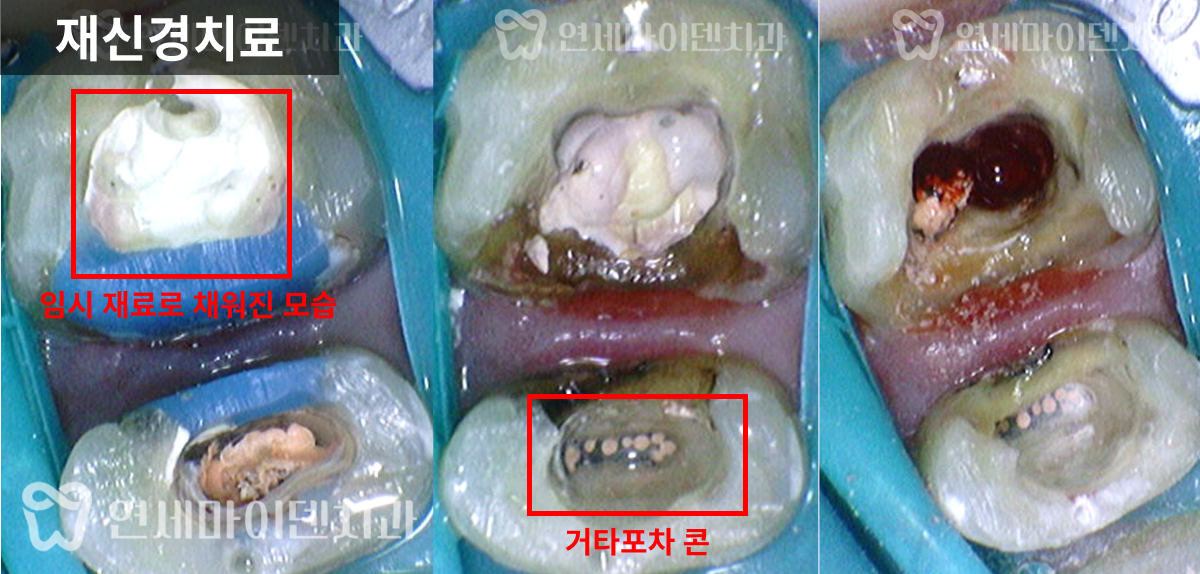

재신경치료를 위해 치아를 뜯어보니, 파란색으로 레진코어가 되어있었습니다.

*파란색은 레진의 종류인데, 과거 어금니 치료는 치아와 보철물의 색 구분을 위해 파란색으로 사용하는 경우가 많았습니다. 이렇게 해두면 나중에 재치료할 때 의사가 구분하기 편하기 때문입니다. 다만 저희처럼 현미경으로 치료하다보면, 레진을 치아색으로 덮어놔도 치아와 레진 구분이 어렵지 않기 때문에 저희는 그냥 치아색 나는 레진을 사용하고 있습니다.

그런데 레진 치료가 원칙적으로 되어 있지 않았습니다.

치아 내부에 레진이 아닌 IRM(Intermediate Restorative Material)과 ZOE(Zinc Oxide Eugenol) 같은 임시 재료가 채워져 있었고, 표면만 얇게 레진으로 덮여있었습니다.

다만 해당 임시 재료는 치아와 제대로 접착되지 않으며, 현재는 주로 임시 충전재로만 사용되기 때문에, 이런 방식은 레진 코어의 본래 목적을 달성할 수 없습니다.

예상대로 레진과 치아사이 접착이 제대로 이루어지지 않아 그 틈으로 충치가 시작된 것이었고,

환자 분의 치아 문제는 다시 원칙적인 치료로 개선할 수 있을 것이라 판단했습니다.

그리고 앞쪽 치아의 신경치료 방식을 보니 거타포차 콘(GP cone)을 하나씩 삽입하는 오래된 방식으로 이뤄져 있었습니다. 오래된 방식이라고 반드시 나쁜 것은 아닙니다. 다만 현재 훨씬 개선된 치료법이 존재하기 때문에 환자분들께서 더 완성도 높은 치료를 받으실 수 있습니다.

거타퍼차 콘(GP cone)을 하나씩 꽂는 방식이 아닌, 수직 가압 충전법을 사용하여 거타퍼차 콘을 녹여 충전하는 현대적 방식으로 진행하였습니다. 레진 충전시에도 임시 재료 없이 원칙적인 치료로 진행했습니다.